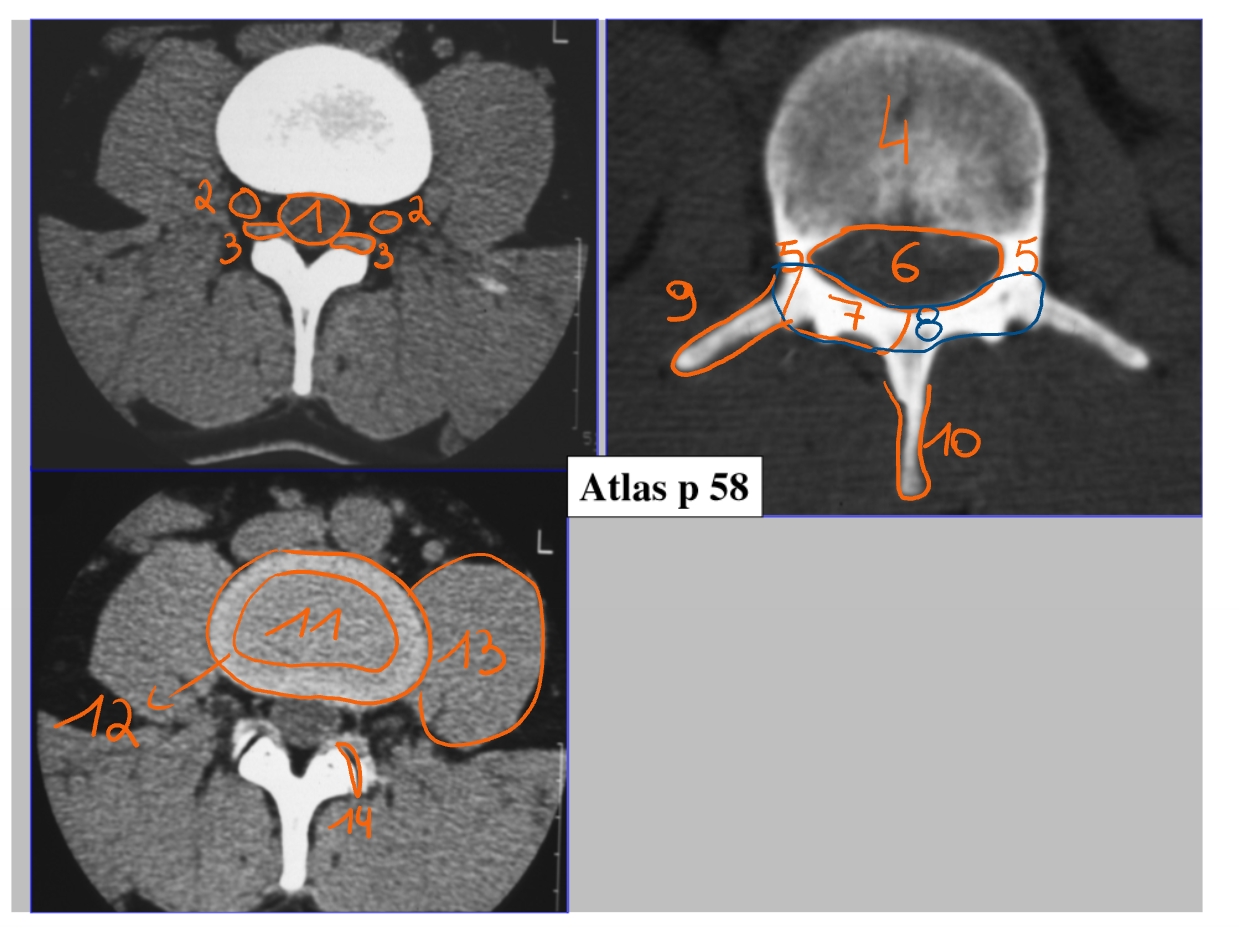

CT-scan → dwarse doorsnede

durazak

ganglion spinale

ligamentum flavum

elastisch ligament, nodig om te buigen

flavum = geel

corpus

pedikel

canalis vertebralis

daarin: cauda equina + ruggenmerg → omgeven door durazak

lamina

arcus

processus transversus

embryologische rest van een rib

processus spinosus

nucleus pulposus

annulus fibrosus

psoas

facetgewricht